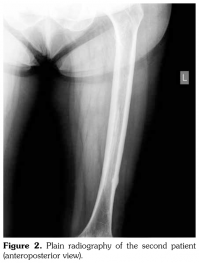

Case 2– A 61-year-old female patient presented with anterior thigh pain and difficulty in walking. Pain severity was 7 over 10 point according to visual analog scale. She had been treated with alendronate 70 mg per week with calcium plus vitamin D for two years. Plain radiographs of femur were taken upon clinical presentation. Cortical stress reaction was detected in both femoral shafts on plain radiographs (Figure 2). Computed tomographic imaging was performed to rule out fracture (Figure 3). Bone scintigraphy showed increased uptake in distal (1)/3 ends of femoral shafts (Figure 4). Serum calcium value was normal and urinary deoxypiridinoline level was mildly increased (46 nM/mMCre).

Typical femoral periosteal stress reaction was described as cortical thickening in the lateral side of the subtrochanteric region. In addition, Kwek et al.(5) found bilateral findings of stress reactions or fractures on plain radiographs in 53% of patients on bisphosphonate therapy. In both of our patients, we observed cortical stress reaction bilaterally.

Radiologically, femoral periosteal stress reaction is described as the presence of the dreaded black line which is a transverse black line traversing the cortex that can be complete or incomplete.(6-9) Magnetic resonance imaging findings of femoral periosteal stress reaction include focal cortical thickening, bone edema, focal cortical resorption cavities and dreaded black line. There is an association between radiographic findings and the presence of clinical symptoms.(10) Similarly, our patients had thigh pain and difficulty in walking.